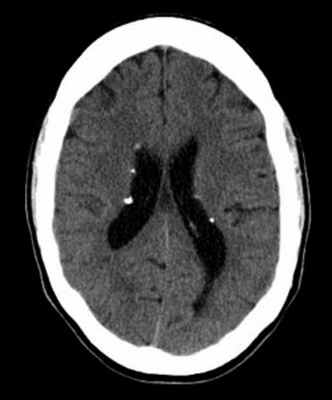

Наиболее типичными нарушениями в головном мозге являются корковые туберсы и субэпендимарные узлы. Туберсы могут быть как единичными, так и множественными, располагаются в виде выступов над единичной или прилегающими бороздами коры, расширяя их. Субэпендимарные узлы локализуются в стенках боковых желудочков и, реже, в стенках III и IV желудочков мозга. У новорожденных субэпендимарные узлы редко бывают кальцифицированными. По мере роста ребенка наблюдается постепенное отложение кальция в субэпендимарных узлах.

Субэпендимарные узлы в 10% случаев трансформируются в гиганто-клеточную астроцитому, которые манифестируют обычно между 5 и 10 годами жизни, имеют тенденцию к росту и локализуются у отверстия Монро

Субэпендимарные кальцификаты и корковые туберсы на КТ головного мозга ребенка с туберозным склерозом

КТ головного мозга при туберозном склерозе. Видны кальцинированные субэпендимальные узелки в стенках боковых желудочков.